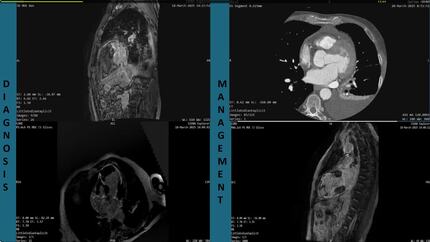

Cardiac rupture identified during cardioembolic stroke: a late complication of myocardial infarction